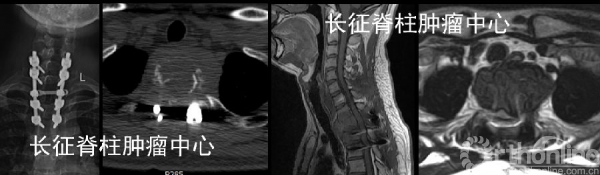

当地医院行后路胸2椎体次全切除取髂骨植骨重建内固定术,术后5月,X线,CT及MRI均提示胸1-3椎体溶骨性破坏,考虑胸2肿瘤组织残留、复发并侵及邻近椎节。